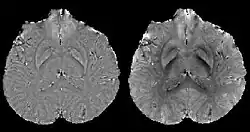

COSMOS assumes a model-free susceptibility distribution and keeps full fidelity to the measured data. This method has been validated extensively in in vitro, ex vivo and phantom experiments. Quantitative susceptibility maps obtained from in vivo human brain imaging also showed high degree of agreement with previous knowledge about brain anatomy. Three orientations are generally required for COSMOS, limiting the practicality for clinical applications. However, it may serve as a reference standard when available for calibrating other techniques.

MEDI has also been validated extensively in phantom, in vitro and ex vivo experiments. In an in vivo human brain, MEDI calculated QSM showed similar results compared to COSMOS without statistically significant difference.[15] MEDI only requires a single angle acquisition, so it is a more practical solution to QSM.